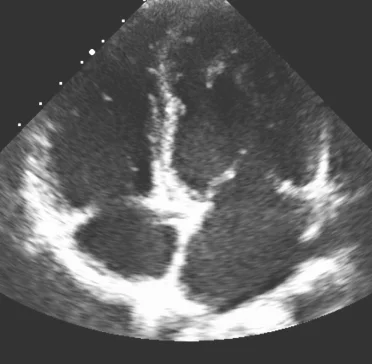

Echocardiogram (“Echo”)

Echo is a common, noninvasive test that uses soundwaves (ultrasound) to create an image of your heart to measure its size and shape and how well it squeezes and relaxes.

Echo can’t directly measure the pressure in your heart—that’s something only a right heart cath can do.

An Echo can indicate the need for a right heart cath to look more closely at the pressures in your right heart